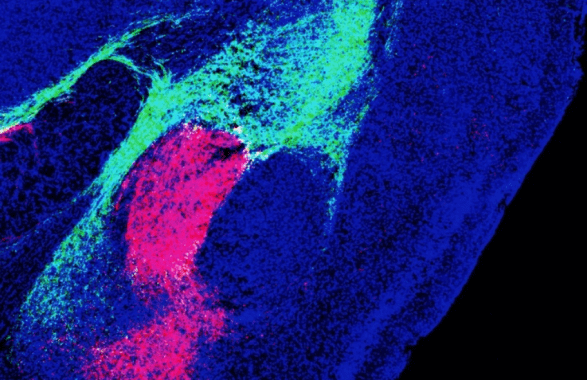

I ricercatori del Salk Institute ci sono riusciti misurando nei topi l’attività di singoli neuroni che si trovano in regioni del talamo e del tronco encefalico dove abbonda una molecola legata all’avversione, il cosiddetto peptide correlato al gene della calcitonina (Cgrp). Usando proteine fluorescenti, hanno ricostruito i percorsi che portano gli stimoli sensoriali negativi fino all’amigdala: sono due circuiti distinti, entrambi necessari per formare ricordi che tengano lontani dai pericoli.